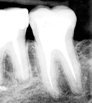

Le but est de reconstituer artificiellement suffisamment de volume à une dent délabrée pour qu’elle puisse servir de soutien à une future couronne prothétique.

— Soit en une séance de façon directe : cette technique consiste à sceller un (des) tenon(s) (pivots) dans la ou les racine(s), puis à les enrober du matériau de reconstitution.

— Soit de façon indirecte par un inlay-core, en deux séances. Cette fois, après avoir préparé la dent, le praticien en fait l’empreinte. L’inlay-core est réalisé dans un laboratoire de prothèse. Il est donc scellé dans la dent de façon définitive lors d’un second rendez-vous.